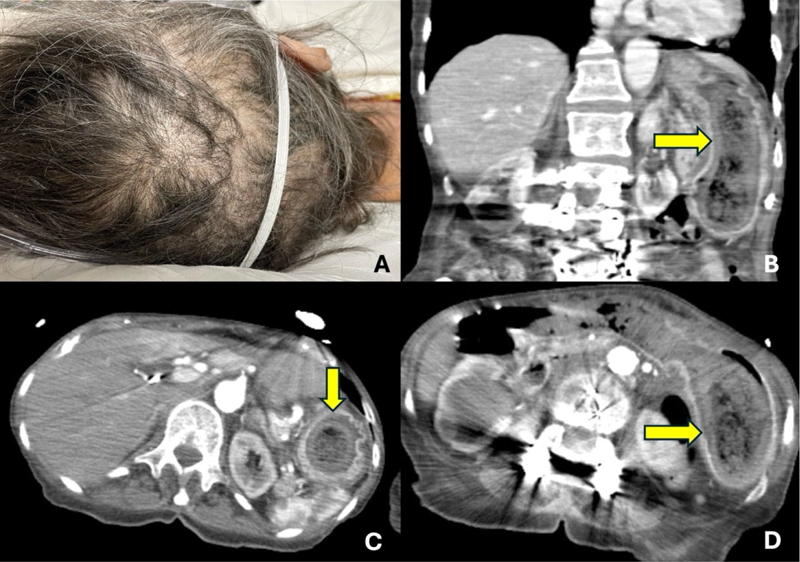

A 77-year-old woman with a history of schizophrenia presented to the hospital with epigastric pain for two weeks associated with a 40-pound weight loss over the past six months. Physical examination showed thinning of the hairline (Figure 1A) and tenderness at the epigastrium. Laboratory tests showed iron deficiency anemia and hemoglobin 10.7 g/dL. Computed tomography of the abdomen with contrast showed abnormal gastric wall thickening and heterogenous mass within the stomach (Figure 1B and C). Esophagogastroduodenoscopy showed a large amount of hair in the gastric body and antrum along with one 15 mm clean based ulcer at the anterior wall of the stomach (Figure 2). Abiopsy from the gastric ulcer showed no evidence of malignancy. The patient was treated with pantoprazole twice daily, and the psychiatry team was consulted for evaluation of trichotillomania.

Figure 1

Figure 1. A: Physical examination shows patches of hair loss that are irregular in shape and broken hairs with different lengths. B: CT coronal plane shows the stomach distended (yellow arrow) with a large heterogenous mass lesion and show internal dense and air foci. C and D: CT axial plane shows a heterogenous mass in the stomach (yellow arrows) with air bubbles and internal dense foci. Gastric wall thickening was noted.